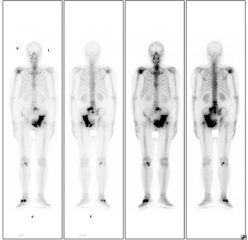

患者老年男性,因前列腺癌骨转移伴明显疼痛,于2022年8月行全身骨显像,后给予锶89及唑来膦酸等联合治疗,疼痛明显缓解,于2023年5月行全身骨显像复查,病灶明显减少、范围缩小、病灶活跃程度减低。